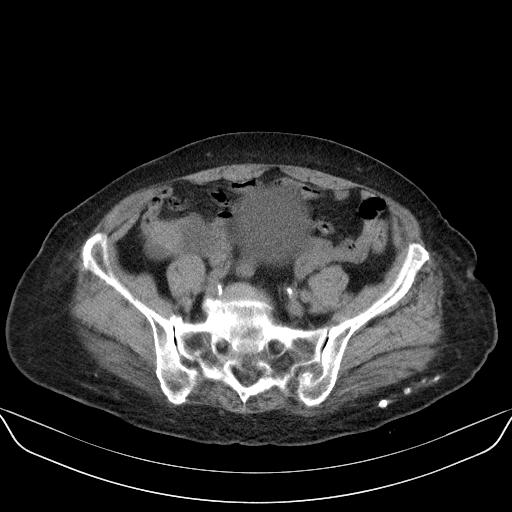

以下是引用yuhongjun在2010-3-12 6:32:00的发言:[br]回肠末端间质瘤,不除外阑尾粘液囊腺瘤,臀部注射性肉芽肿钙化. [br] [br]